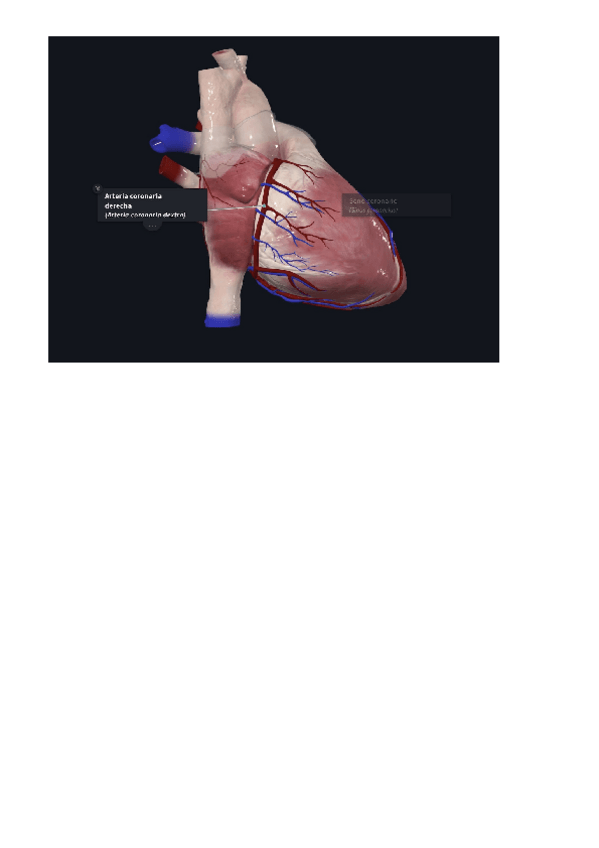

Practica-3.pdf